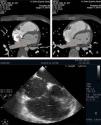

Caso 2Doente do sexo masculino de 50 anos, com antecedentes de diabetes mellitus tipo 2, fibrilhação auricular permanente e queixas de dor torácica, foi referenciado para realização de angioTC cardíaca para exclusão de doença coronária. O exame revelou doença coronária não significativa, AE dilatada e imagem de subtração no apêndice auricular esquerdo (Figura 2), sugestiva de trombo. Apesar de não ter sido realizada uma segunda passagem poucos minutos após a primeira aquisição, o que permitiria confirmar o diagnóstico de trombo, não foi realizado ecotransesofágico com este propósito, uma vez que o resultado não iria alterar a orientação terapêutica. O doente tinha indicação para iniciar anticoagulação oral que iniciou nessa altura.

Caso 3Doente do sexo masculino de 58 anos com doença coronária conhecida, tendo sido submetido a angioplastia da descendente anterior proximal no passado. Apresentava recorrência de angor pelo que foi referenciado para realização de angioTC cardíaca com intuito de avaliar a patência do stent. O exame excluiu progressão da doença coronária, revelou hipertrofia assimétrica do ventrículo esquerdo, com septo interventricular medindo 36mm (Figura 3), alterações compatíveis com miocardiopatia hipertrófica. O doente foi submetido a implantação de um cardiodesfibrilador e até ao momento não se registaram terapêuticas apropriadas.